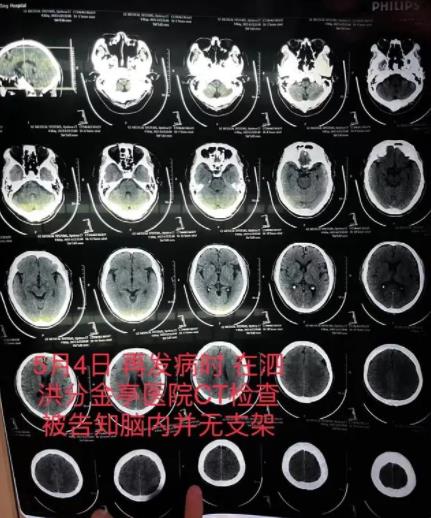

朱老漢的出院收費票據(jù)及部分明細。朱先生供圖老人突然發(fā)病,醫(yī)生承認支架植入失敗5月4日,朱老漢突發(fā)嚴重腦梗。他先被救護車送至江蘇省宿遷市泗洪縣分金亭醫(yī)院搶救。令家屬沒想到的是,當時的CT檢查發(fā)現(xiàn),其顱內(nèi)段部分動脈已嚴重堵閉,同時未發(fā)現(xiàn)此前植有支架。“我們當時不相信這個檢查結(jié)果,認為這是小醫(yī)院,可能檢查不出來,所以我們決定轉(zhuǎn)送到之前的醫(yī)院。”朱先生說,朱老漢又被轉(zhuǎn)入宿遷第一人民醫(yī)院,曾作為主刀醫(yī)生的齊某此時才承認,之前未能在患者顱內(nèi)血管成功植入支架。

朱老漢在泗洪縣分金亭醫(yī)院的CT檢查報告,顯示顱內(nèi)并無支架。朱先生供圖“說實話,我做了這么多手術(shù),沒做成的時候很少,當時這個支架沒放成,我覺得很打臉,感覺有點不好看,下不了臺。”在朱先生提供的錄音中,齊某承認患者顱內(nèi)沒有支架,也不知道支架究竟在何處。他說,支架一般預裝在微導管上,但在手術(shù)過程中,導管抵達病變處被推出時,并沒有看到支架自動釋放撐開的顯影,“360度轉(zhuǎn)圈就是看不到,這是第一次遇到(這種情況)”。錄音中,齊某猜測,可能是支架存在出廠質(zhì)量問題,或在推送過程中出現(xiàn)脫載的情況,也有可能支架始終“就在微導管里”。但當家屬詢問其是否留存了微導管,齊某稱,“已經(jīng)扔了。”據(jù)中國醫(yī)師協(xié)會心血管內(nèi)科醫(yī)師分會指南與共識工作委員會、中青年冠狀動脈專家沙龍組織專家2019年制定的《冠狀動脈支架脫載的處理和預防專家共識》,冠狀動脈支架脫載與病變、器械和技術(shù)操作等因素密切相關(guān),目前支架脫載的發(fā)生率極低,已降至1%以內(nèi),但所導致的“次生”并發(fā)癥發(fā)生率達20%,可導致腦血管意外、急性心肌梗死、甚至死亡。